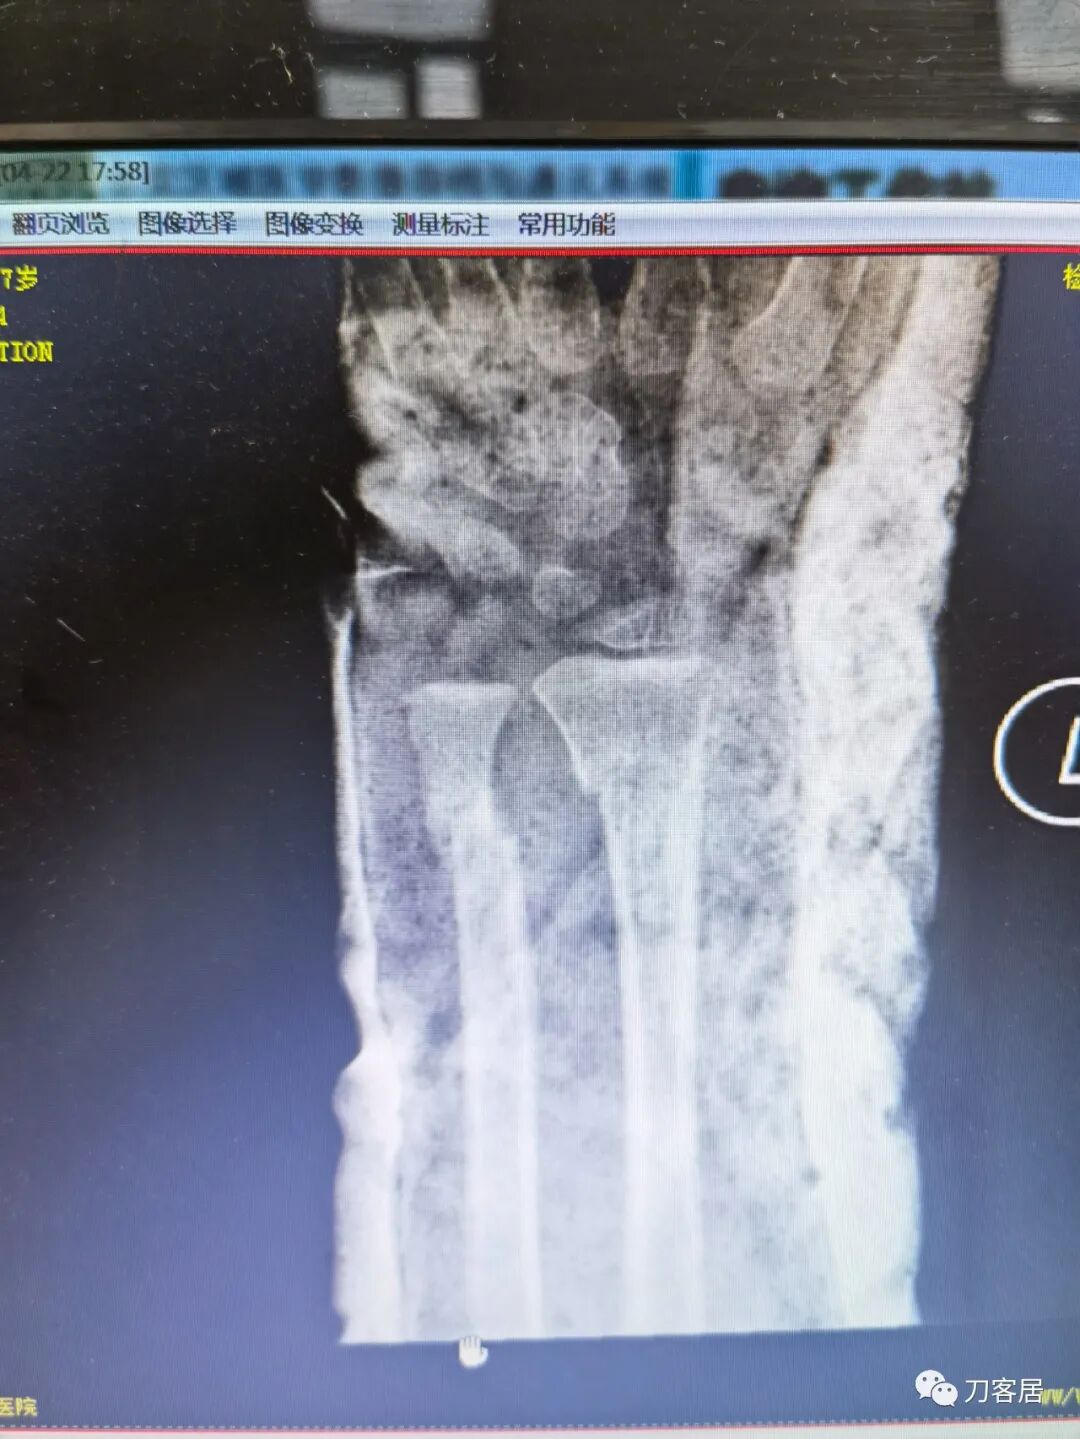

2021年7月21日,在中华骨科网儿童骨科病例讨论群里,看到了几张图片,是某仁慈医院的一位手外科医生做的手术,被某地器械厂家发在朋友圈里炫耀,有小儿骨科医生看不过去,就发群里请大家评论,引起众多小儿骨科医生的批评。

下面是这个6岁孩子,尺桡骨远端双骨折的术前及术后片子和外观照片。

1.  这是一个很简单的6岁儿童无移位的尺桡骨远端骨折。没有皮肤损伤,没有移位,没有骨折碎块儿。

2.  这个骨折处理起来也很简单,单纯的打石膏托或者中医的小夹板,或者正规的包括腕关节和肘关节的管型石膏外固定4周即可治愈该骨折。实在不行,如果这个孩子比较听话,不太调皮的话,用一本书,一个三角巾悬吊固定4周,都可以治愈该骨折。但是给这个患者用外固定架做了手术,而且桡骨远端的几颗克氏针距离骨折线太近,其中一枚克氏针进入到骨折间隙内。从这个术中图片来看,术者的外固定手术技术也有待于进一步的提高。毕竟术者应该还很年轻。从X线片来看,前臂及手的尺侧有不透光影,应该还使用了外固定石膏绷带托,而且我猜测应该是高分子的石膏绷带托,这个是纯属猜测,不一定是对的,不过如何解释前臂尺侧的不透光影呢?如果真是用了石膏绷带外固定的话,那为啥要做手术呢?外固定架术后就不该再用石膏绷带托辅助了。